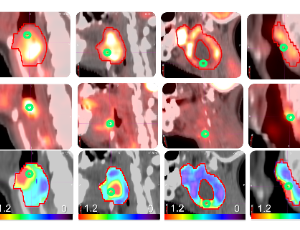

The tumor dose sensitivity matrix and stem cells in head and neck cancer

Radiation therapy (RT) is one of the pillars of locally advanced head and neck cancer (HNSCC) treatment in combination with cisplatin or epidermal growth factor receptor inhibitors. Despite a very high local tumor control rate, approximately 50% of patients with locally advanced disease will develop a recurrence.

Arch Stem Cell Ther, 2023, Volume Volume 4, Issue Issue 1, p1-4 | DOI: 10.46439/stemcell.4.018